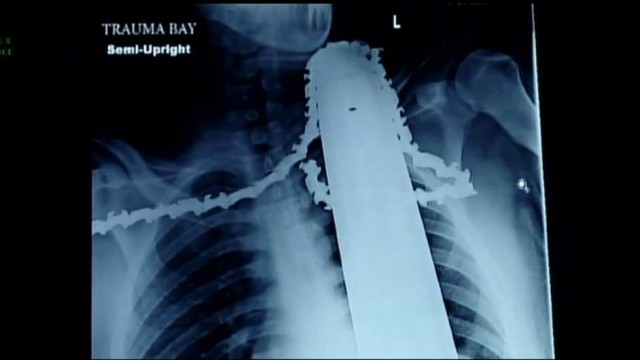

Дървар оцеля, след като острието на моторна резачка влязло на няколко сантиметра във врата и рамото му.

21-годишният Джеймс Валентайн от американския щат Пенсилвания бил част от екип, който режел дървета в понеделник следобед, когато резачката отскочила и го прерязала, предаде „Скай Нюз”, цитирана от Би Ти Ви.

Колегите му успели да го свалят от дървото и го откарали в болница. Лекарите отстранили мотора на резачката, но оставили острието, за да не се стигне до значителна кръвозагуба.

Острието не е засегнало сънната артерия на пациента и е нанесло повече наранявания на рамото му, което го е спасило.

Според медиците няма опасност за живота на младежа и ще му трябват няколко седмици, за да се възстанови напълно.